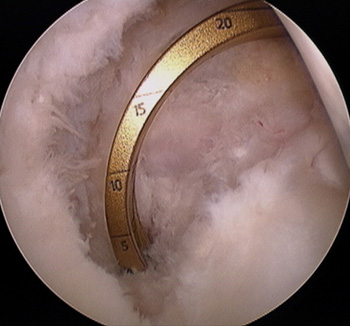

maestu1_fig2

Figura 2: Vista artroscópica desde portal anterolateral de túnel en cóndilo medial para plástica a una banda de LCP en una rodilla izquierda.